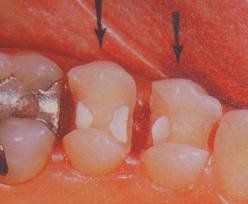

適應症

一般來說能用充填法修復的牙體缺損都是嵌體的適應證。具體來說:嵌體適用於有牙體缺損但牙髓健康,對修復材料性能及修復效果要求高,不願意接受充填治療或充填治療反覆失敗的患者。

由於嵌體是只能修復缺損部位的牙體而不能保護剩餘部分的牙體的修復體,所以嵌體只能在牙體雖缺損,但尚有較大體積的健康牙體組織餘留時套用。也就是說作嵌體的牙冠必須有足夠的高度和餘留牙壁的厚度以使其獲得固位與抗力。